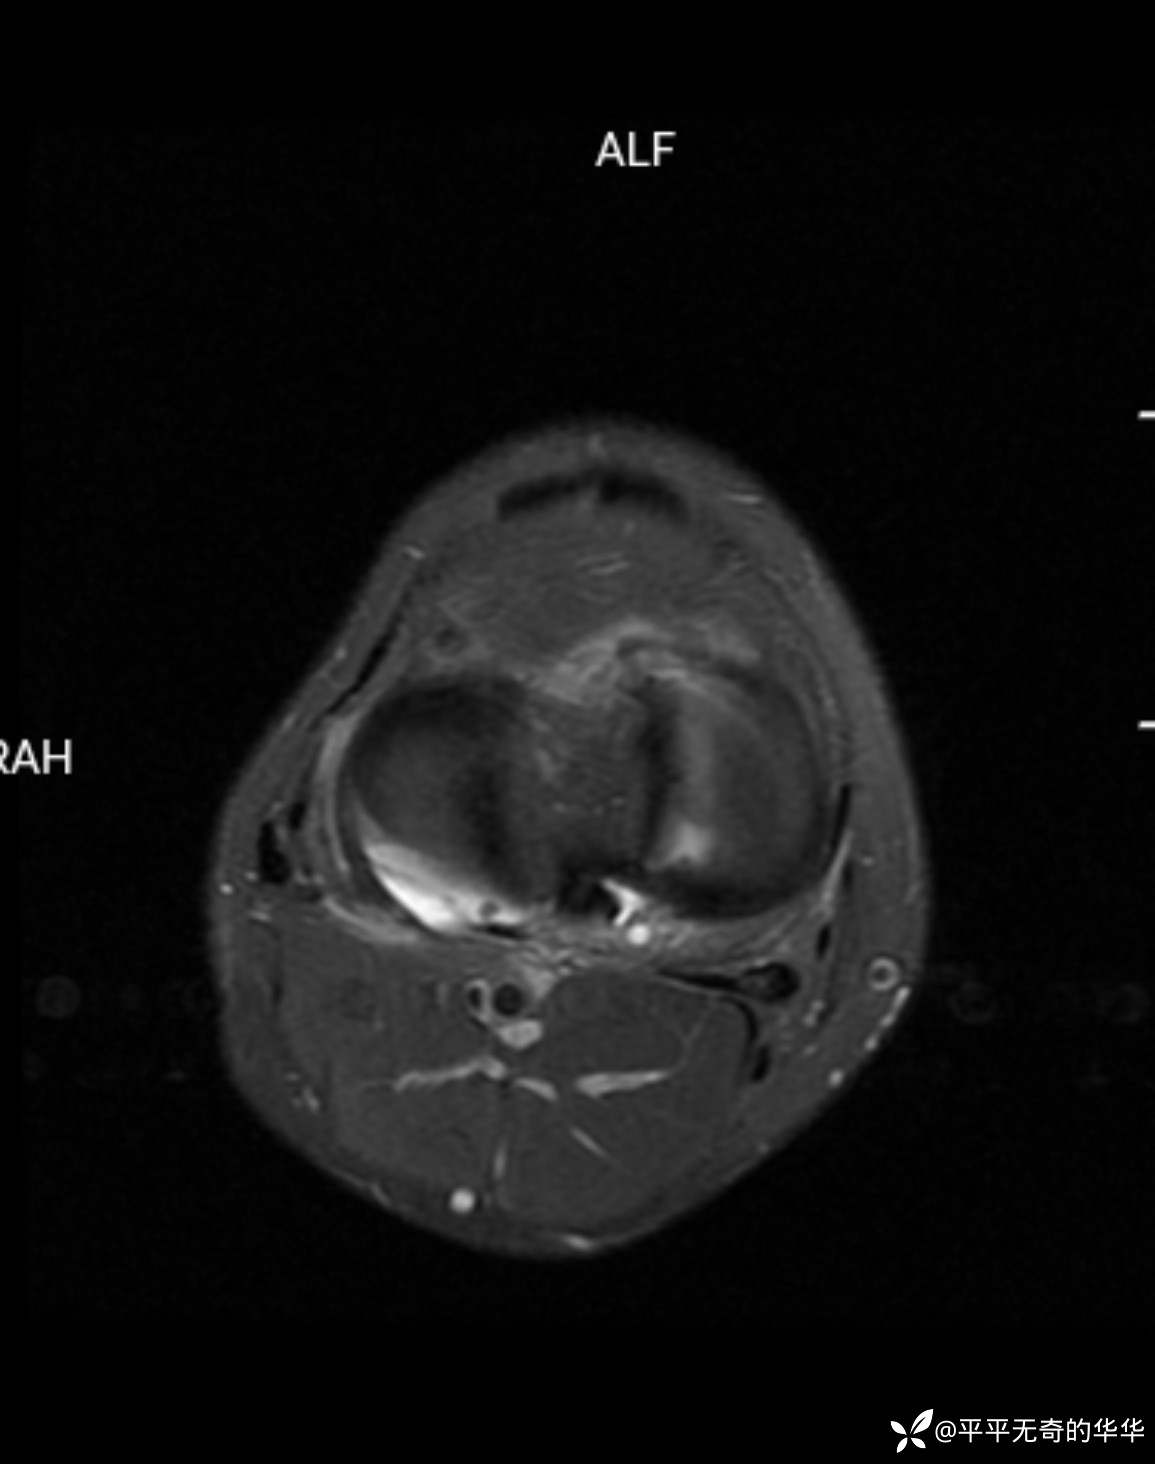

辅助检查:膝关节平片未见异常。磁共振影像如下。